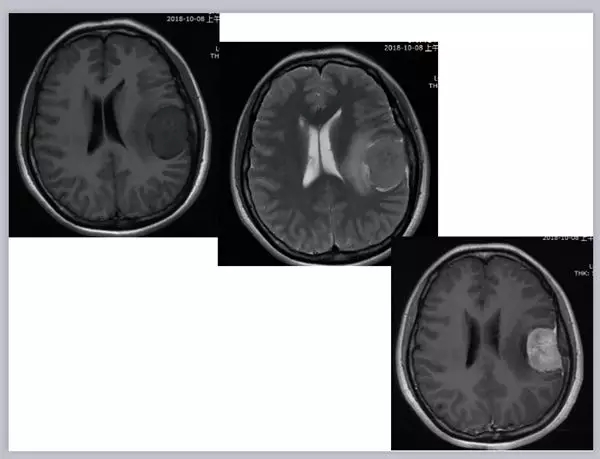

肿瘤患者